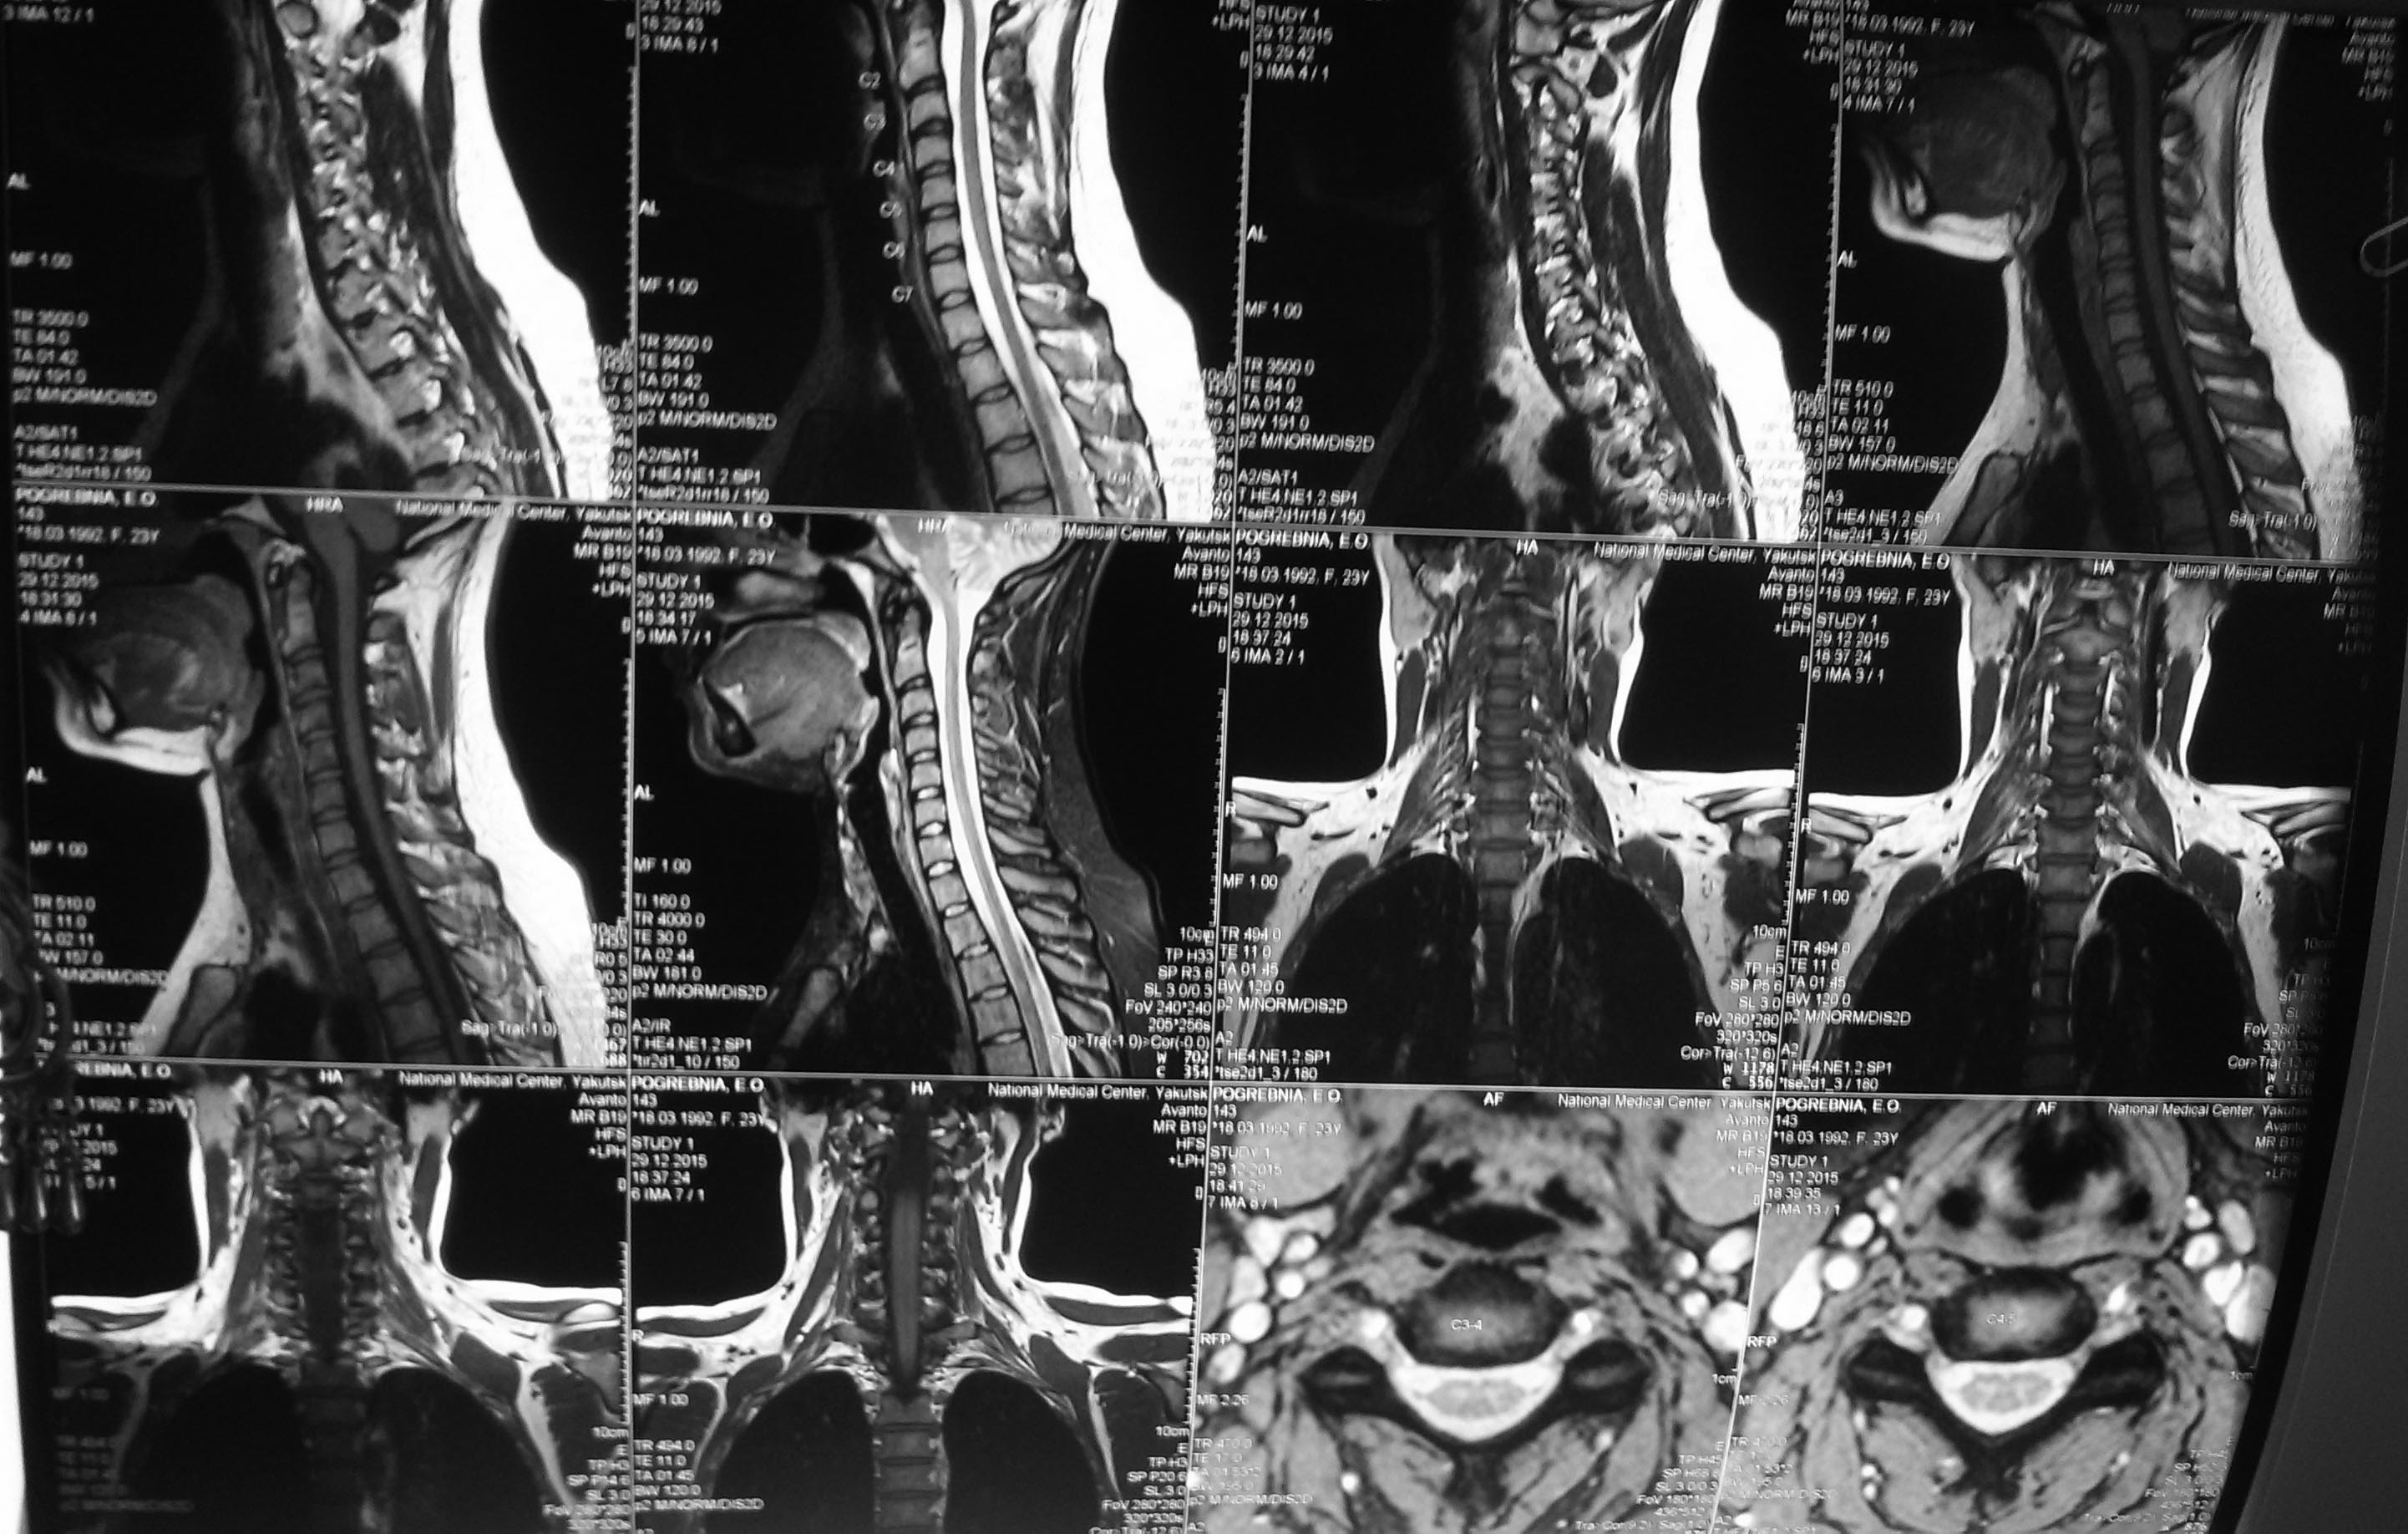

Обратилась девушка 23 лет с жалобами на боли в области н/3 левого плеча. По МРТ отек костного мозга в н/3 плечевой кости. Остеосцинтиграфия - накопления РФП нет, РКТ - очагов деструкции нет. Боли сохраняются и после пробной антибактериальной терапии.

Боли беспокоят с июля 2015 г. Постепенно усиливаются, сперва были жгучие, сейчас стали распирающего характера, периодически ощущает пульсацию. Бывает гипостезия 2-3 пальцев, но не постоянная. Отмечает усиление болей в вечернее и ночное время. По МРТ ШОП - хондроз в сегментах С3-4, С4-5, С5-6. Выпрямление шейного лордоза. ЭНМГ - сегментарные вегетативные расстройства. Выраженное антидромное снижение возбудимости мотонейронов передних двигательных спиномозговых корешков с признаками мотонейронального состояния на уровне С6, с периферической вторичной аксонопатией n. radialis слева. По ананлизам тромбоцитоцитоз до 500, СОЭ 12 мм/ч, остальные показатели в норме. Консультирована гематологом, неврологом. Все свое исключили. Какие будут мысли о дальнейшей диагностике? От предложенной биопсии пока воздерживаются. Какой предварительный диагноз?